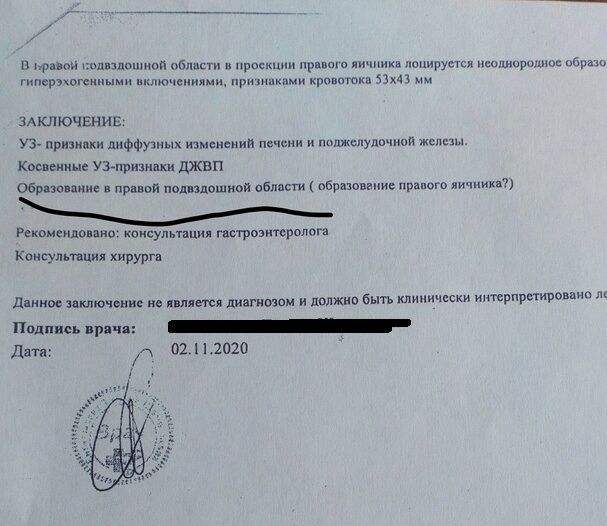

Новообразование так и не иссекли и смолянка до 2020 года ходила с постоянной температурой и болью. Кроме того, девушка похудела на 15 килограмм. Обращение в Железнодорожную больницу дало небольшой результат — пациентке рассказали, что все это время она живет с постаппендэктомическим инфильтратом, то есть скоплениями крови и лимфы в месте прошлой операции.

После обследования в Петербурге стало ясно, что в животе девушки обнаружен кальцинат размером в 5,5 сантиметров, то есть скопление солей кальция в органах. Обычно их размер доходит до нескольких миллиметров.